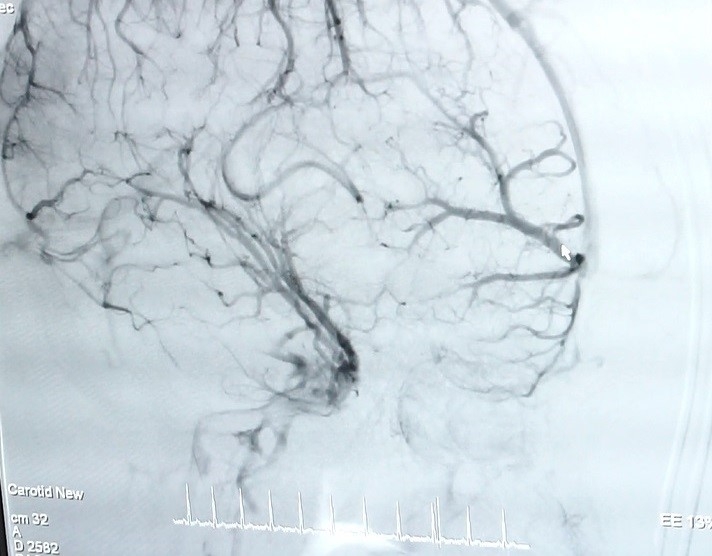

| Hình ảnh mạch máu não của bệnh nhân |

TS.BS Trần Chí Cường, cố vấn chuyên môn tại Trung tâm Đột quỵ CIH-SIS Bệnh viện Quốc tế City cho biết, dị dạng mạch máu (AVM) vô cùng nguy hiểm bởi có thể gây ảnh hưởng đến chi phối của não bộ lên hoạt động cơ thể, nếu phát hiện và điều trị muộn có thể dẫn đến tử vong. Bệnh nguy hiểm nhưng nếu được chẩn đoán sớm có thể điều trị khỏi hoàn toàn. Hiện nay, phương pháp chụp mạch máu não bằng ứng dụng DSA giúp bác sĩ có cái nhìn chính xác về vị trí, kích thước, hình dạng của đoạn mạch dị dạng đồng thời vẽ được biểu đồ huyết mạch nơi mạch máu dị dạng phát sinh và xử lý chính xác.